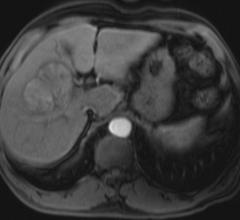

March 16, 2010 - Physicians took new steps toward understanding what patient type would benefit most from Yttrium-90 ...